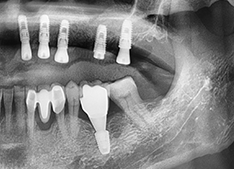

서울탑플란트 치료사례

어떠한 임플란트 케이스도 문제없이 치료가 가능합니다

A2. 임플란트 시술은 CT 촬영으로 잇몸뼈 상태를 확인한 뒤,

인공치근을 식립하고 치유 기간을 거쳐 보철물을 장착하는 과정으로 진행됩니다.

서울탑플란트치과는 3D 디지털 가이드 시스템을 사용하여

절개 범위를 최소화하고 빠른 회복을 유도합니다.